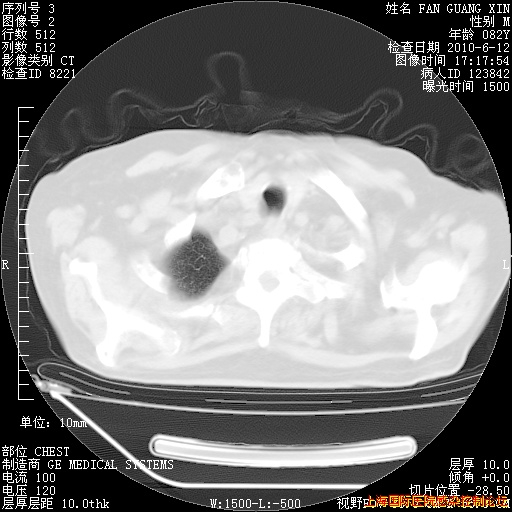

6月12日纵膈窗